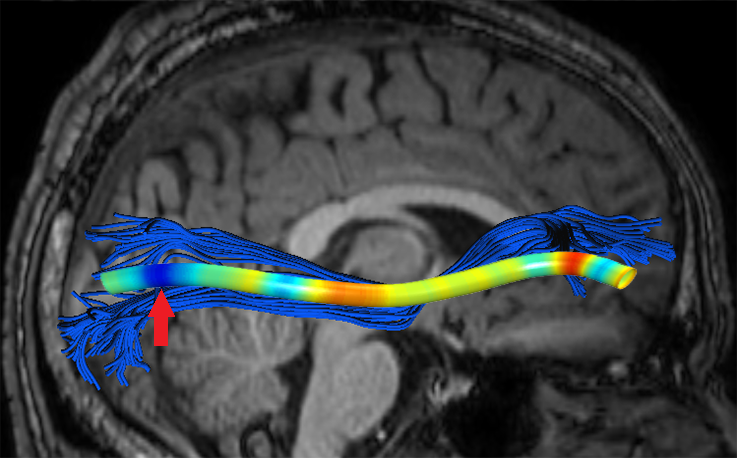

Experiments also showed significant FFDD longitudinal changes between mid-season and post-season scans in some football players. Fig. 7 presents mid- and post-season MD-FFDD profiles comparison of the left IFOF of one of the players, showing increased irregularities over time at the occipital part of the tract. Fig. 8 presents a similar MD-FFDD longitudinal analysis of the FMT of a different player, showing increased irregularities at the central part of the tract.

| Mid vs. Post | Mid-season | Post-season | ||

|---|---|---|---|---|

![]() |

|

STDs |